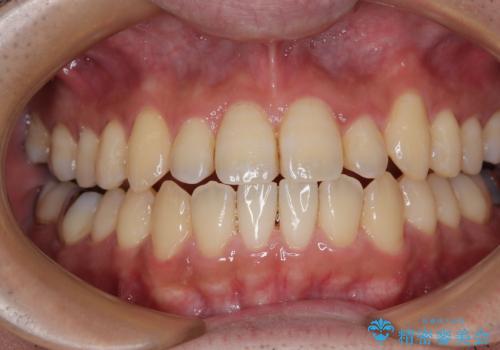

- 前歯のデコボコとクロスバイトを治したいとのことで来院された患者様です。

上下顎ともに歯列全体の側方拡大とIPR(歯と歯の間を削る)によってデコボコとクロスバイトが解消するように設計し、インビザラインにより治療を行うこととしました。

反対咬合特有の治療途中の前歯の干渉が長く続き、治療中に食事をとりにくく、ご迷惑をおかけしました。

前歯の咬み合わせの調整などを行い、安定した咬み合わせに仕上げることができました。